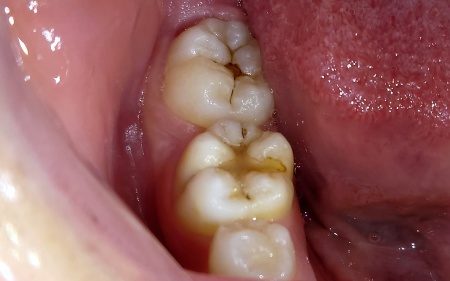

治療前

「右下の奥歯が虫歯かもしれないが、痛みはない」とご相談いただきました。

拝見したところ、右下の奥歯2本に虫歯が見つかりました。

いずれの歯も過去に白い歯科用プラスチックのコンポジットレジンで治療されており、その詰め物の周囲から再び虫歯が生じていました。

虫歯は進行すると歯の内部にある神経にまで影響が及び、強い痛みが出る可能性があります。

こうした場合には神経を取り除く治療が必要になりますが、神経を失った歯は栄養が行き届きにくくなるため、結果として寿命が短くなる傾向があります。

以上のことから、虫歯が進行する前に早めの治療が必要と診断しました。